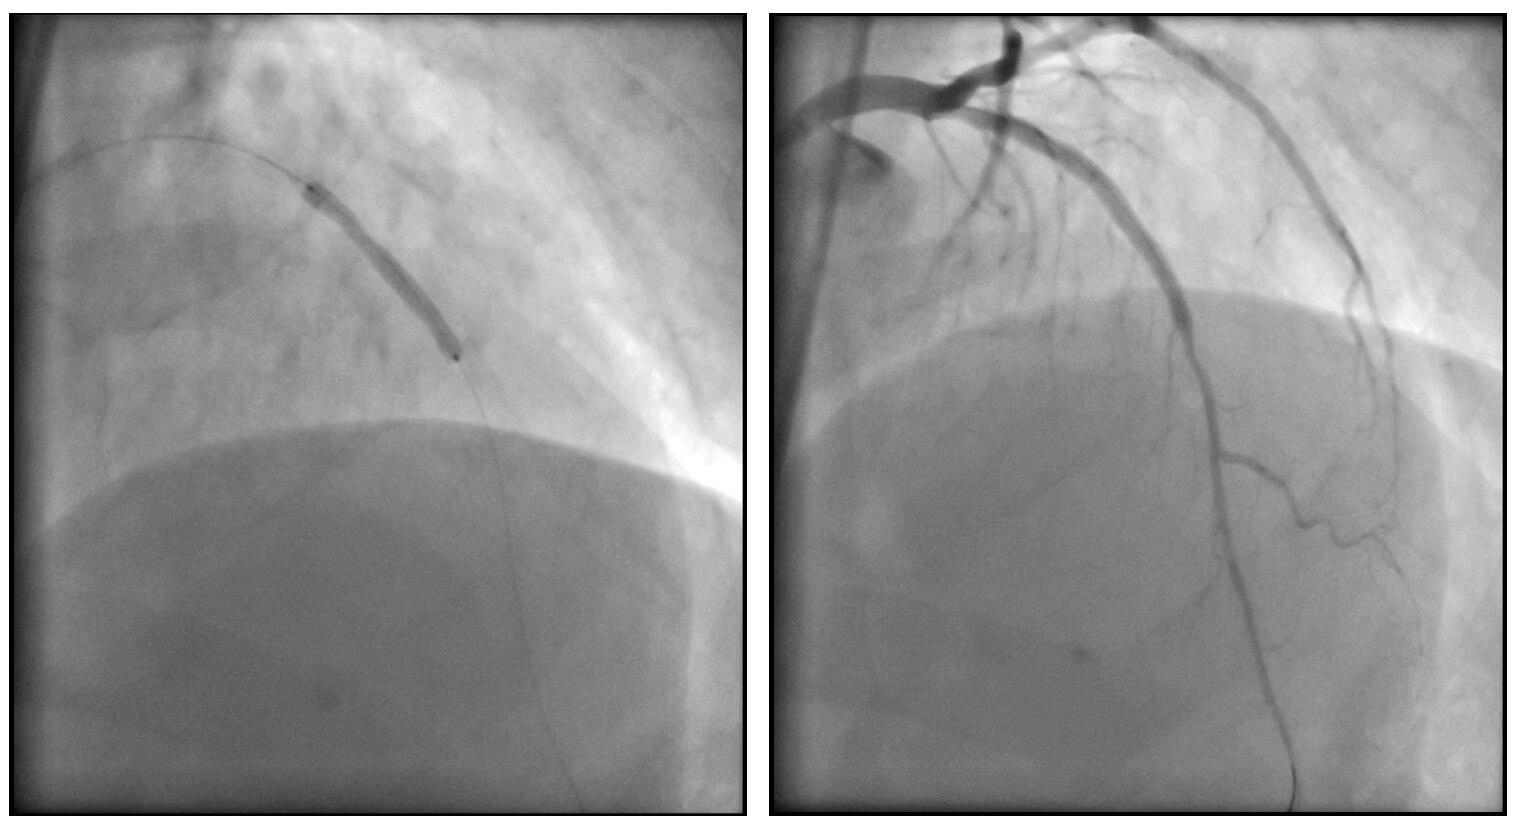

Posteriormente, se logró la predilatación de la oclusión con balones de bajo perfil y se implantó un stent DEStiny en el sitio de la lesión. Tras la apertura de la arteria, se identificó una lesión en la zona de reentrada (sitio de aterrizaje de la guía retrógrada desde la arteria coronaria derecha), por lo que se avanzó una guía por vía anterógrada y se implantó un segundo stent.

Se obtuvo un excelente resultado angiográfico final. El paciente fue dado de alta a las 48 horas del procedimiento, sin complicaciones.